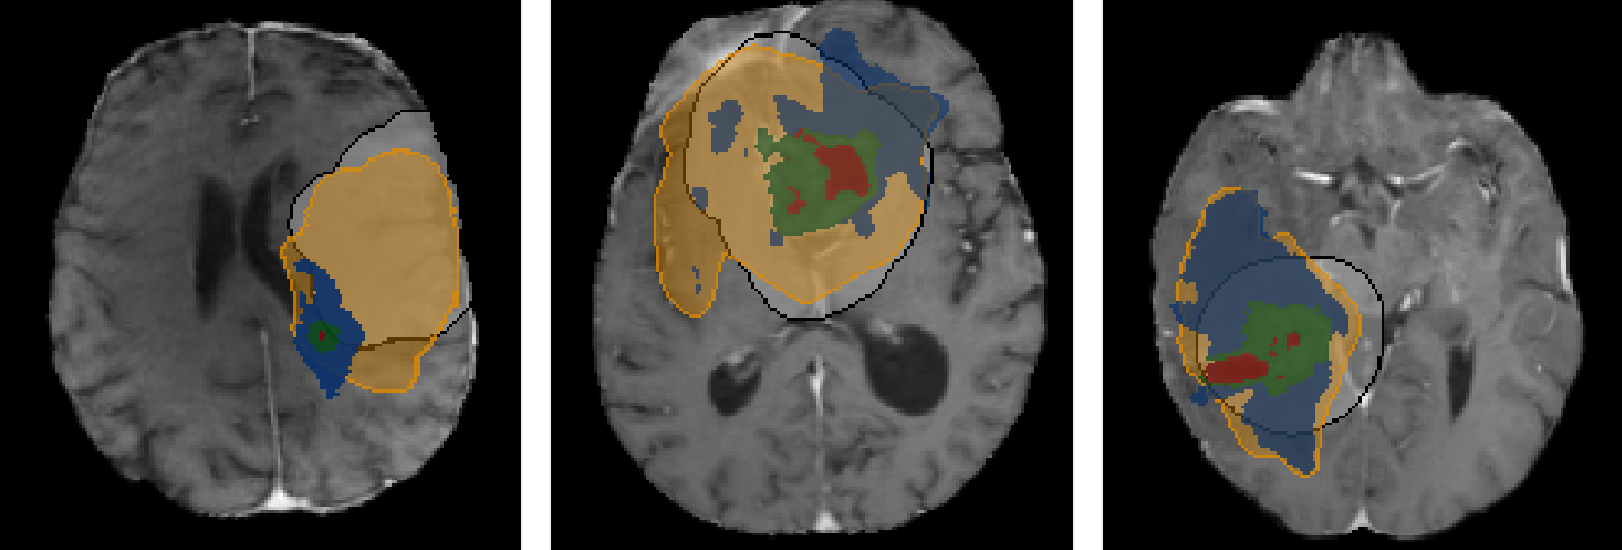

"Brain Tumor Growth Modeling for Radiotherapy Planning"

Accurate modeling of brain tumor growth holds great promise for improving radiotherapy planning by capturing microscopic infiltration that remains invisible on standard imaging. In this talk, I will present a series of advances toward patient-specific biophysical and data-driven models of glioma growth. Our work integrates mechanistic tumor modeling with machine learning to enable accurate, efficient, and individualized predictions of tumor spread. By combining reaction-diffusion formulations with structural information from diffusion tensor imaging, we capture how white matter architecture shapes glioma invasion. A learnable inference framework then bridges these biophysical models with data-driven parameter estimation, enabling fast and robust reconstruction of patient-specific tumor cell distributions from MRI. Together, these developments move toward clinically applicable tumor growth modeling for personalized radiotherapy planning.

Name: Brain Tumor Growth Modeling for Radiotherapy Planning.png

Desc: Brain Tumor Growth Modeling for Radiotherapy Planning.png